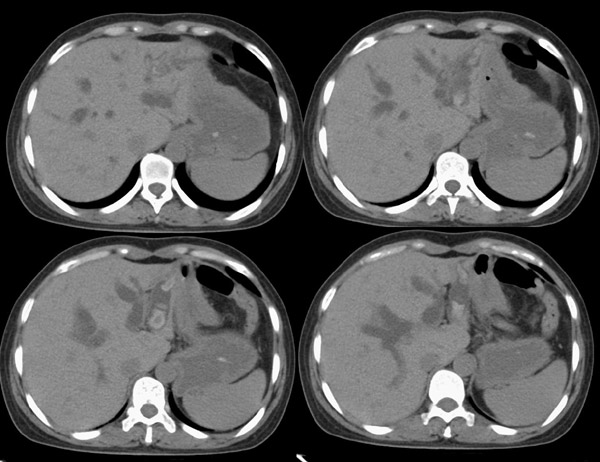

局部1mm薄层重建: